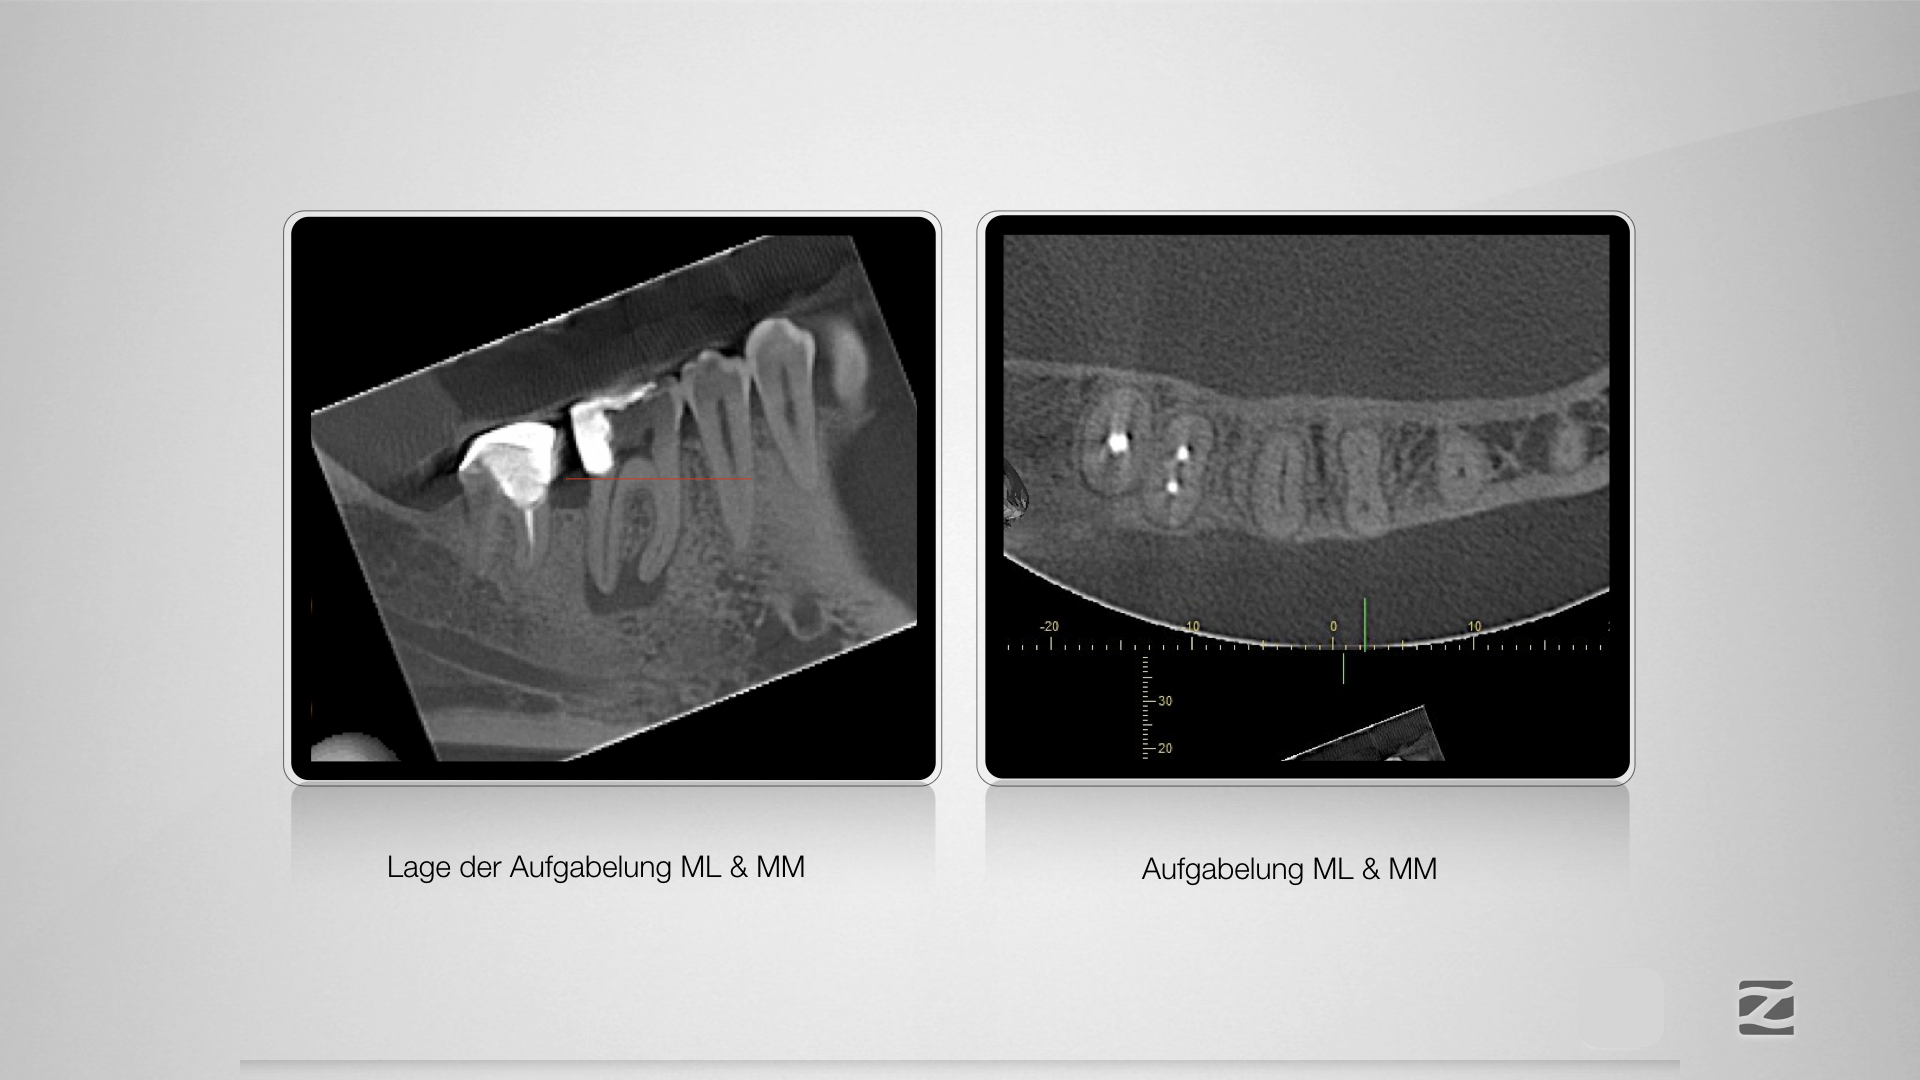

Mit Navigation zum Erfolg